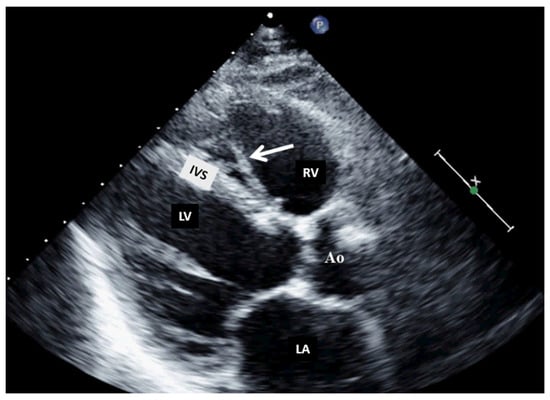

Normal or aberrant structures that may be present in the right cavities include the crista terminalis, a Chiari network (Figure 3) [15], aberrant atrial bands in the right atrium, a moderator band (Figure 4), aberrant papillary muscles, and accessory chordae tendineae in the right ventricle.

Figure 3.

Two-dimensional transthoracic echocardiography (apical 4-chamber view) showing a Chiari network (arrow) in the right atrium before and after (the last image) an electrophysiological study complicated by catheter entrapping in the Chiari apparatus. LA, left atrium; LV, left ventricle; RA, right atrium; RV, right ventricle.

Figure 4.

Two-dimensional transthoracic echocardiography (modified parasternal view, long axis) showing a moderator band in the right ventricle. Ao, aorta; IVS, interventricular septum; LA, left atrium; LV, left ventricle; RV, right ventricle.